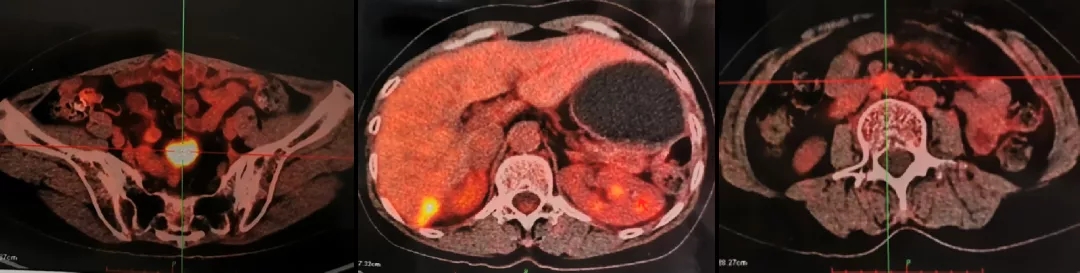

2021.4.23复查CA125上升至70.2U/ml。2021.4.24 CT:肝肾隐窝病灶增大,考虑复发。患者退出BGB-290临床试验。

2021.5.8 PET-CT:肝肾隐窝转移灶。2021.5.12复查CA125水平为95.5U/ml。

PET-CT检查结果